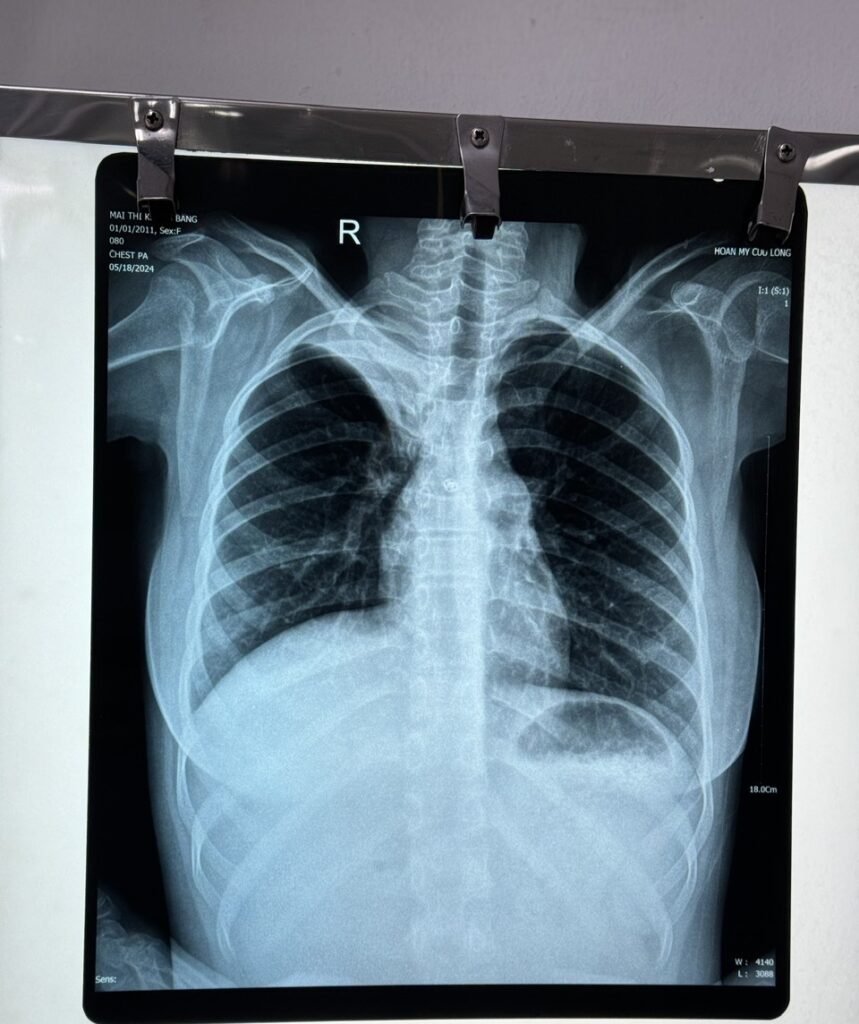

Sau khi thăm khám và thực hiện các cận lâm sàng cần thiết, kết quả X-quang phổi có hình ảnh đám mờ đồng nhất thùy trên phổi phải. Sau đó bé được chụp cắt lớp vi tính MSCT ngực ghi nhận kết quả: xẹp toàn bộ thùy trên phổi phải, kèm thâm nhiễm tạo đám mờ đồng nhất. Các xét nghiệm khác chưa ghi nhận bất thường. Bệnh nhi được chẩn đoán: viêm phổi thùy đỉnh phổi phải.

Hình X-quang trước (trái) và sau 06 ngày điều trị (phải)

Ekip bác sĩ tiến hành hội chẩn, điều trị phối hợp kháng sinh ngay từ đầu, điều trị triệu chứng, trợ sức, tập vật lý trị liệu hô hấp. Sau 10 ngày điều trị, bé dần khỏe hơn, không thở mệt, SpO2 bình thường, ăn uống khá hơn. Khi thăm khám, ghi nhận thông khí đều 2 bên phổi, thông khí đỉnh phổi phải tốt và bé được xuất viện sau đó, uống toa về và tái khám theo hẹn của bác sĩ.